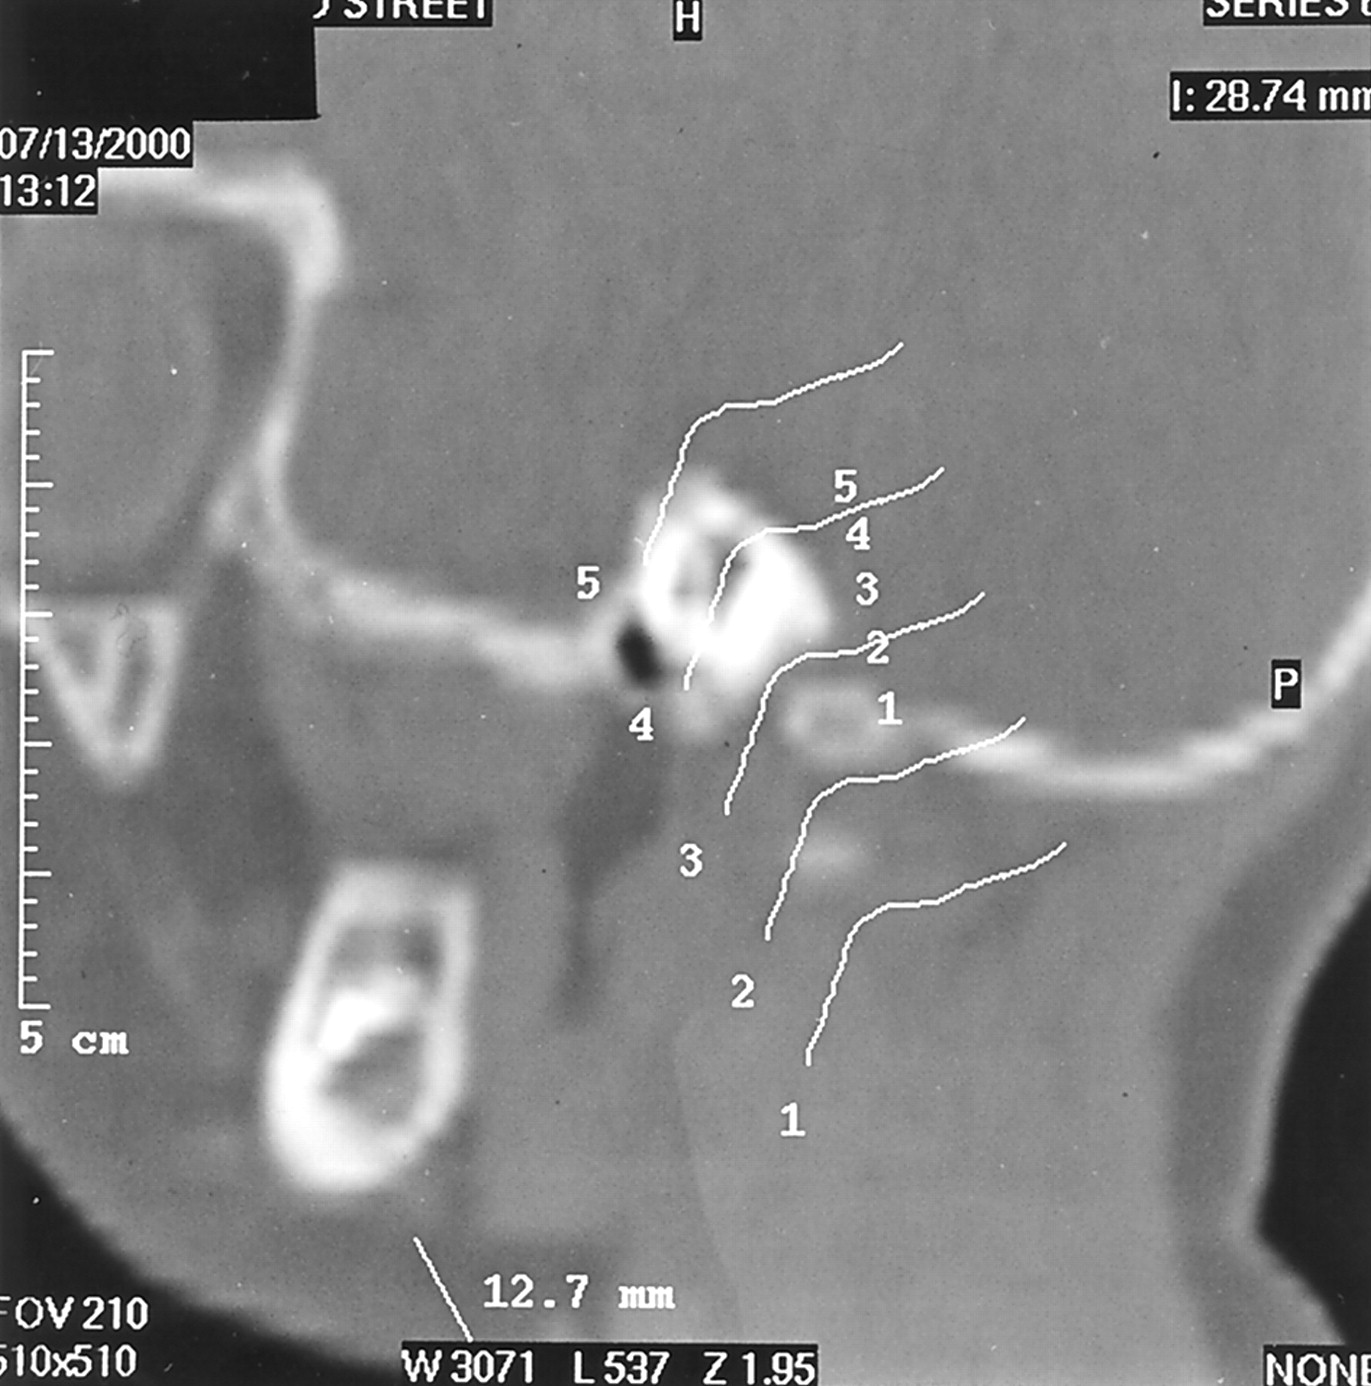

A single pediatric neuroradiologist (P.M.R.) undertook all the image manipulation and measurements, in random order, without reference to clinical details at the time the data were acquired. Multiplanar reformatted images of the skull base were created to allow measurement of the jugular foramina. A set of reformatted parasagittal images was obtained in the line of the jugular foramen, or if the foramen was very tortuous, this was achieved by using freehand drawing and a curved reformat. The second set of images was obtained in a plane orthogonal to the parasagittal images by using the latter as a template (Fig 1). The anatomic plane of the second set of images depended on the orientation of the jugular foramen: axial if the foramen ran horizontally or reformatted coronal-oblique if not. The narrowest point of each foramen was determined by visual inspection of the images, and measurements of the diameter of the foramen at this point were obtained from each of the images (Fig 2). Thus, two orthogonal measurements of the narrowest point of each jugular foramen were obtained, in a parasagittal plane and a second plane orthogonal to the first, be it axial or reformatted coronal-oblique, depending on the exact orientation of the first image plane.

Parasagittal reformatted CT scan obtained through the jugular foramen shows curved line template for production of second reformatted image in the orthogonal plane (lines have been separated for clarity, but during the study, they were all grouped with the foramen).